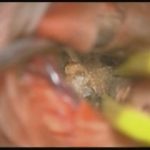

術中写真

摘出 中